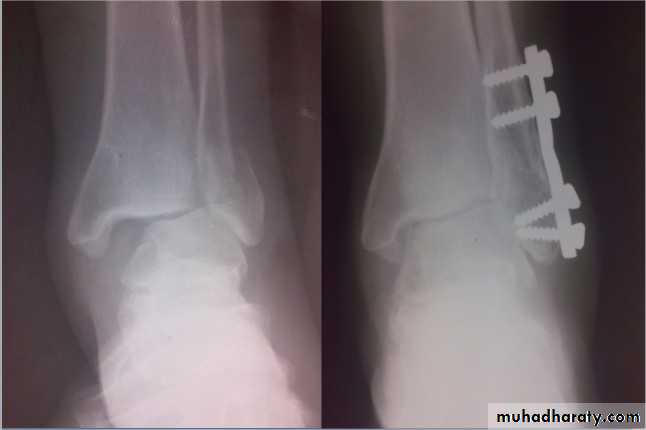

Danis-Weber classification (based on the level of fibular fracture)

Type A: a fibular fracture below syndesmosis and oblique fracture medial maleolus.

Type B: fibular fracture at syndesmosis + disruption of ant. Fibers of tibiofibular lig. + fracture of medial malleolus or rupture of deltiod lig.

Type C: fibular fracture above syndesmosis+ tibiofibular lig. (syndesmosis) is torn. Unstable fracture-subluxation of ankle mortise.

DANIS WEBER CLASSIFICATION OF ANKLE FRACTURES

Principals of treatment

Treatment within hours or after several days until swelling subside by elevation and splintage.Anatomical reduction is a must to avoid later osteoarthritis.

Fibular fracture below tibiofibular lig. Ankle jt. is stable; reduce the fracture and immobilize in a cast.

Fibular fracture above tibiofibular lig. Ankle jt. is unstable; usually need internal fixation.

Medial maleolus fracture fixation